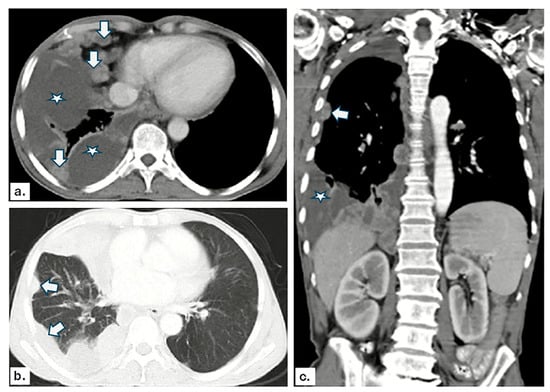

3.2. US and CT Findings in MPE

3.4. Validity of US and CT Findings in Detecting MPE

3.5. Logistic Regression Analysis for MPE